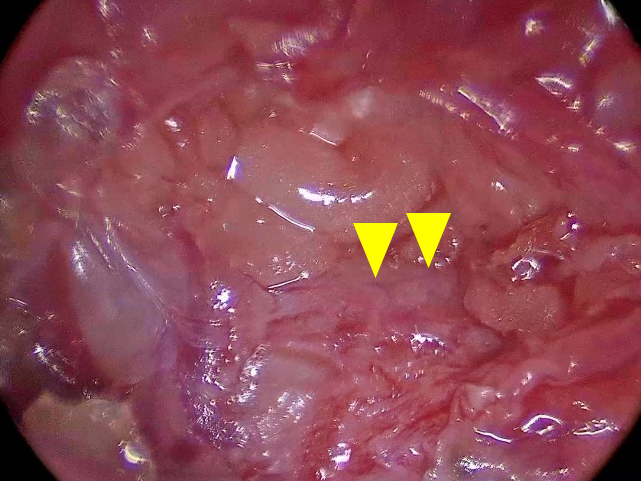

水色のものが胸管CT上では2本に分岐(黄矢頭)

ICG染色法では4本に分岐(黄矢頭)